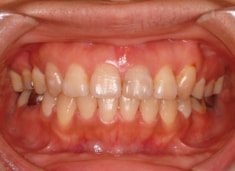

治療前

治療後(2年5ヶ月後)